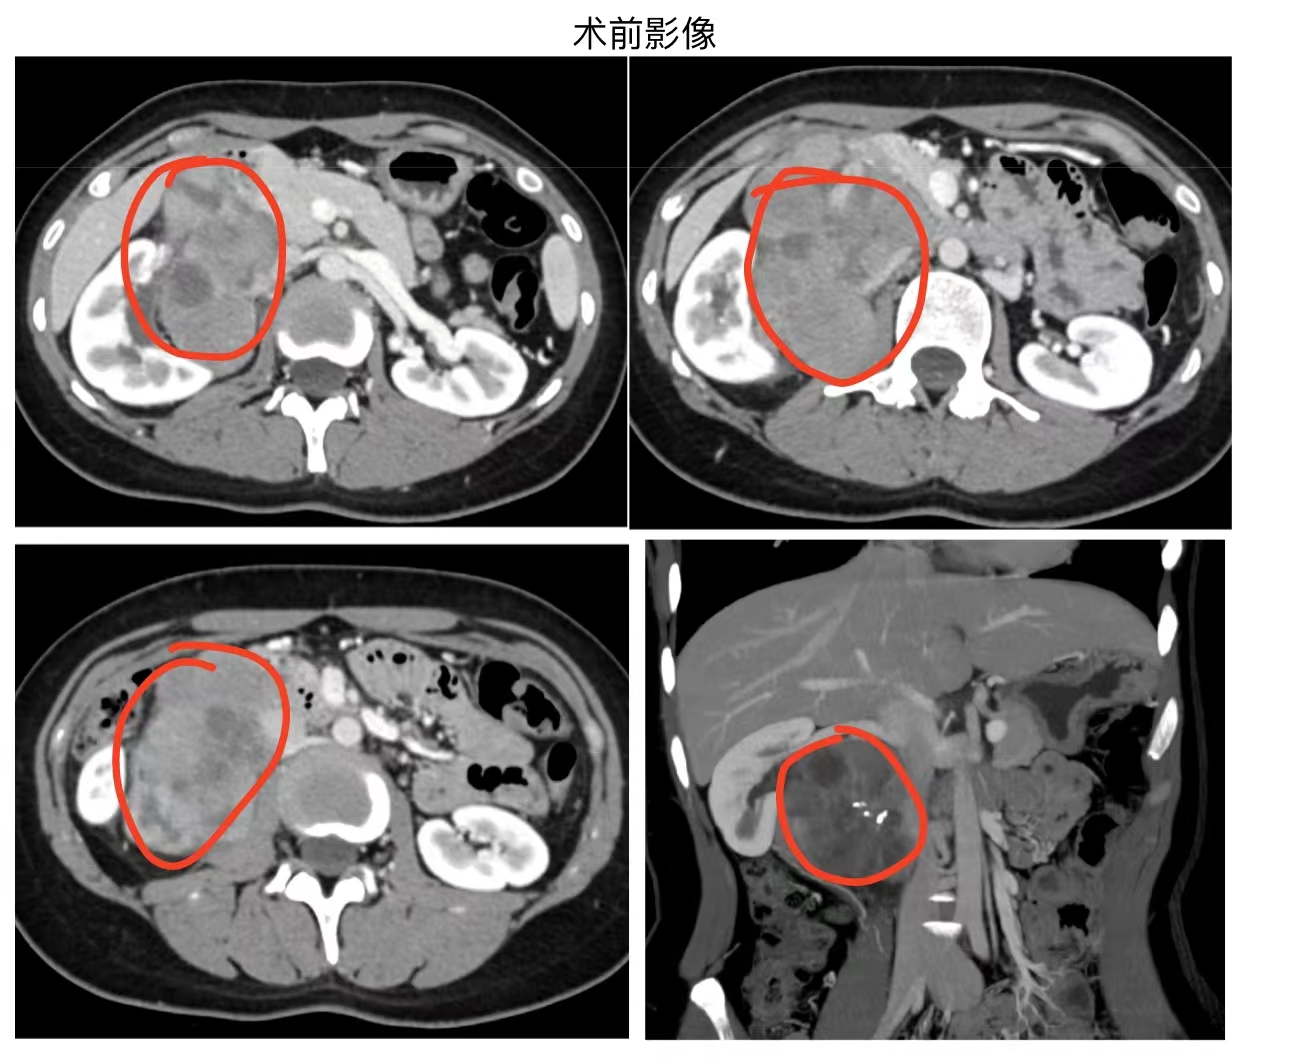

据悉,该患者在一个多月前无意中发现右上腹有一约鸡蛋大小的包块,且无腹痛、发热等症状。经当地医院检查,发现腹膜后一大小约9cm包块,且包块已压迫下腔静脉并包绕右侧肾门。穿刺活检结果显示为平滑肌肉瘤(腹膜后肿瘤的一种),当地医院认为手术难度大且难以保肾,建议先进行化疗,为此患者极度焦虑,天天饱受病痛和心理折磨。

然而,患者经过一个疗程的化疗后,肿瘤病灶并未出现明显变化。于是,患者慕名来到真人电子网址普外一(肝胆胰血管外科)杜晓炯教授门诊。杜晓炯教授在仔细阅读影像学资料并充分评估后,认为尽管肿瘤情况复杂,但仍有机会通过手术进行切除。

经过充分的术前准备,患者于3月中旬顺利进行了手术。术中,杜晓炯教授团队发现肿瘤已侵犯下腔静脉2/3周径,遂行下腔静脉肿瘤切除及人工血管置换;肿瘤部分包绕右肾,肾盂积水,经过精细的分离操作,成功分离出右侧肾动、静脉及输尿管,完整切除了肿瘤,保留了患者的肾脏。整个手术过程顺利,术后患者恢复良好,一周后顺利出院。